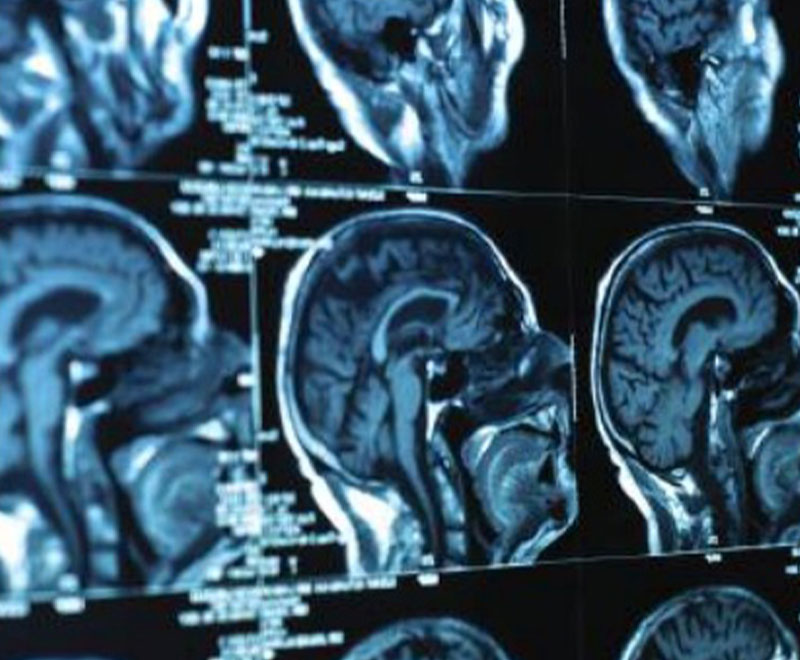

Brain Tumor Vaccine Shows Promise in Trials

A vaccine that jump-starts the immune system is showing promise in keeping patients diagnosed with glioblastoma, or malignant glioma, alive longer.